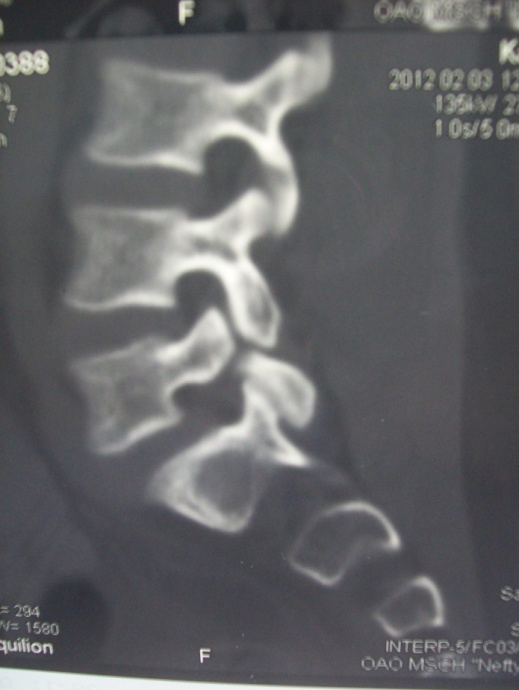

The lumbar spine lateral X-ray and tomographic images illustrate this condition as a gap between the superior and inferior articular processes of the fifth lumbar vertebra (see the photo).

Photo of 16 year-old patient M., engaged in Greco-Roman wrestling for 4 years (a), and his lumbar spine computer tomographic image (b). Pars interarticularis defect in the LV vertebra (spondylolysis)